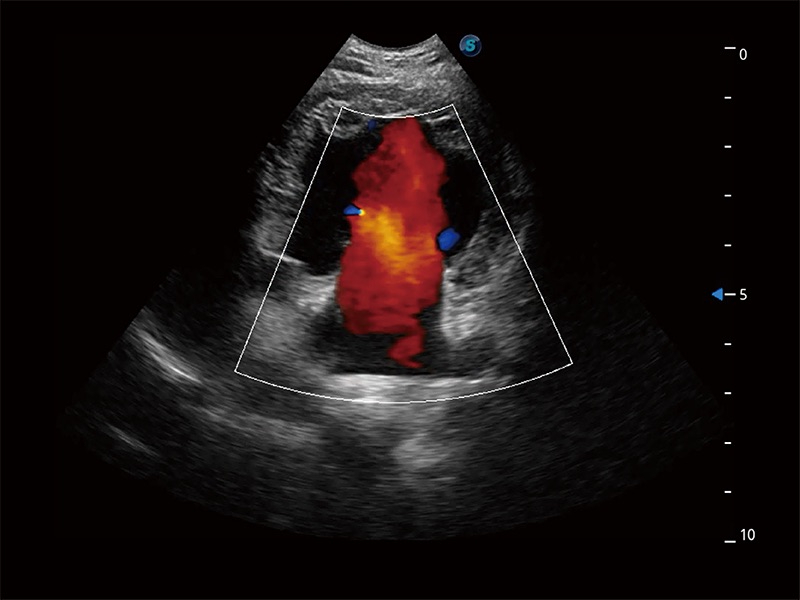

ProPet 80 配備了豐富的心臟探頭群、先進(jìn)的成像技術(shù)和專業(yè)的心臟測(cè)量工具,可幫助動(dòng)物醫(yī)生為不同體型和生理結(jié)構(gòu)的動(dòng)物提供心臟和心肌功能的全面評(píng)估。

實(shí)時(shí)用顏色表示心肌組織運(yùn)動(dòng),觀察和定量組織的運(yùn)動(dòng)情況,對(duì)快速檢測(cè)與評(píng)估心肌的灌注和活性、電傳導(dǎo)及心肌收縮和舒張功能等均能提供重要的診斷信息。